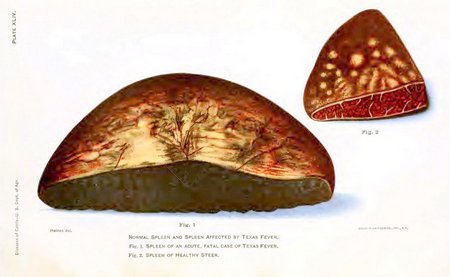

| XLIV. Normal spleen and spleen affected by Texas fever | 504 |